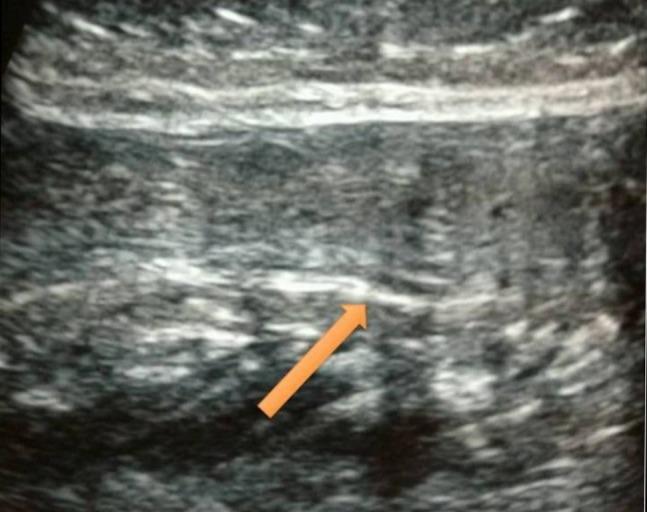

The Achilles tendon is the strongest tendon in the body, which is commonly ruptured in male athletes. Bilateral rupture of the Achilles tendon is a rare condition with very few reported cases in the literature. It poses a challenge in management, and hence, we report a case with traumatic bilateral Achilles tendon rupture in a young male patient and its management. One side was treated conservatively as the rupture was partial and the other side, which had a complete tear, was operated. At nine months follow-up, the patient has had a satisfactory result and is now bearing full weight without any problems. We suggest this method of treatment to be worthwhile for this unusual entity.

跟腱是人体最强壮的肌腱,在男性运动员中常发生断裂。双侧跟腱断裂是一种罕见的情况,文献报道的病例很少。它在治疗上具有挑战性,因此,我们报告一例年轻男性患者创伤性双侧跟腱断裂及其治疗情况。一侧因断裂为部分性而采用保守治疗,另一侧完全撕裂则进行了手术。在九个月的随访中,患者取得了满意的结果,现在能完全负重且没有任何问题。我们认为这种治疗方法对于这种不寻常的情况是值得的。